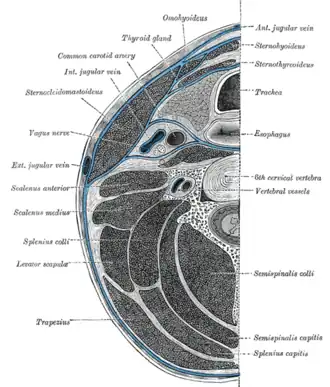

Section of the neck at about the level of the sixth cervical vertebra

Section of the neck at about the level of the sixth cervical vertebra -

The right and left vagus nerves descend from the cranial vault through the jugular foramina,[5] penetrating the carotid sheath between the internal and external carotid arteries, then passing posterolateral to the common carotid artery. The cell bodies of visceral afferent fibers of the vagus nerve are located bilaterally in the inferior ganglion of the vagus nerve (nodose ganglia).The vagus runs parallel to the common carotid artery and internal jugular vein inside the carotid sheath.